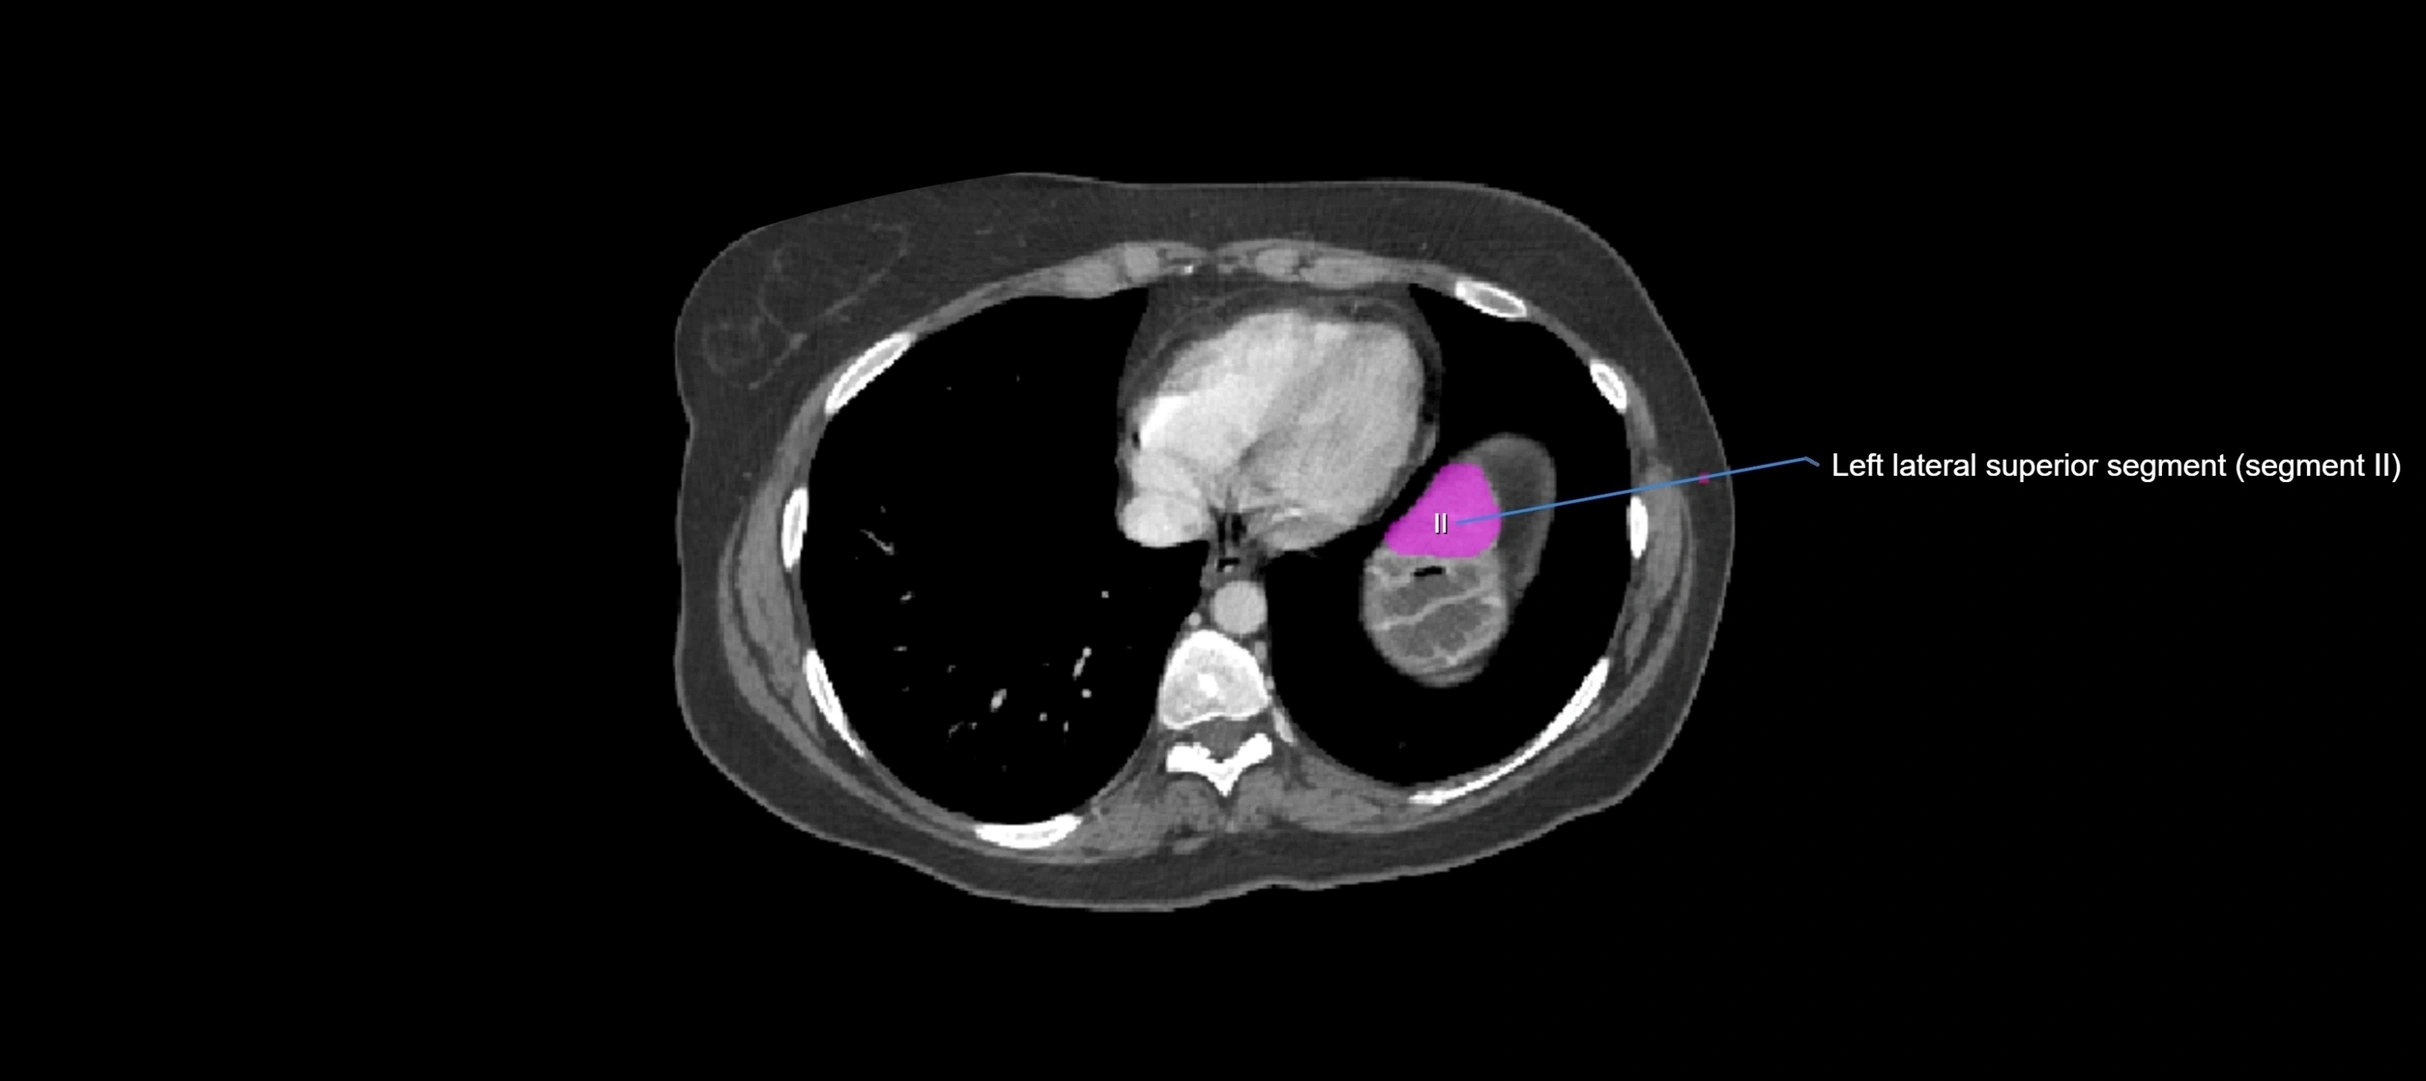

Caudate lobe of liver

The caudate lobe of the liver is a distinct anatomical subdivision of the liver, designated as segment I in Couinaud’s classification. It lies on the posterior surface of the liver, between the fissure for the ligamentum venosum (left boundary) and the groove for the inferior vena cava (IVC) (right boundary). Superiorly, it is related to the posterior liver surface, and inferiorly it is separated from the left lobe by the porta hepatis.

The caudate lobe is unique because it receives dual portal venous and arterial inflow from both the right and left portal veins and hepatic arteries. It also has independent venous drainage directly into the IVC via multiple small hepatic veins, unlike other lobes that drain through the three main hepatic veins.

This anatomical autonomy makes the caudate lobe especially significant in liver surgery, transplantation, and hepatic venous outflow obstruction syndromes (e.g., Budd–Chiari syndrome). Enlargement of the caudate lobe is a characteristic imaging feature in chronic liver disease and cirrhosis.

MRI image

image